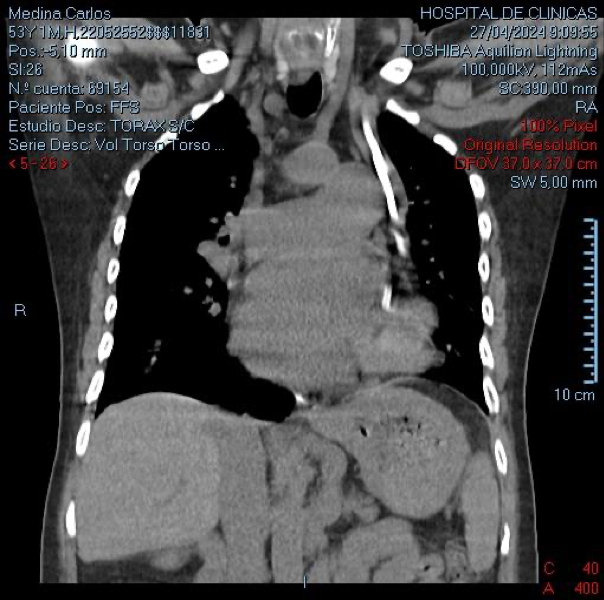

La TAC mostró una vena cava superior izquierda y otra derecha

Además de la anomalía vascular de la vena porta y de las cavidades cardíacas que presentes en este paciente, se detectó una anomalía vascular en las venas centrales. Se debe tener presente la posibilidad de que exista esta asociación de variantes anatómicas cuando debemos abordar vías centrales, en nuestro caso con catéter de doble lumen para tratamiento dialítico. El tip del catéter izquierdo se ubicó a nivel de seno coronario, donde el flujo sanguíneo resultó deficiente para efectuar el tratamiento dialítico. Se adjunta gráfico con esquema de las alteraciones más frecuentes de la vena cava superior doble.(1)